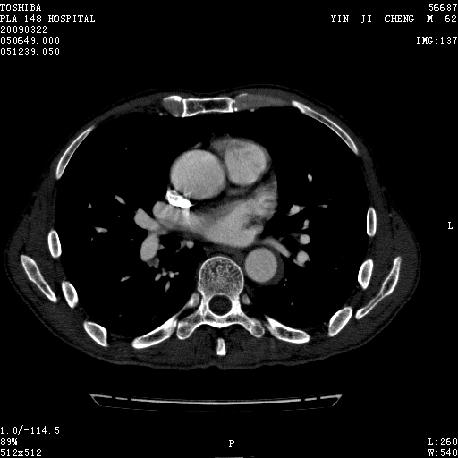

男 62 夜间突然腹痛并向背部放射 ,急诊疑胰腺炎 ,胰淀粉酶正常 ,ct示胰腺未见明显异常,发现降主动脉密度欠均,做主动脉造影示胸腹主动脉半月形低密度充盈缺损,内膜钙化并内移,累及腹腔干致根部明显狭窄,未见明显破裂口。 本人为是不典型夹层,其他人有说是动脉硬化或动脉炎的。请大家发表一下看法。

东芝16排的图像不错!

我觉得这个不像主动脉夹层,应该是血栓多点,如果可以重建个mpr也许对诊断更有帮助。